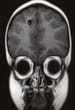

Neuroimaging in neurocysticercosis. Subcortical parenchymatous cysticercosis